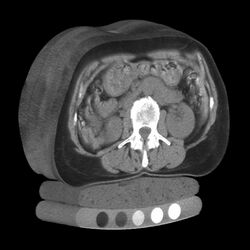

Tomography is imaging by sections or sectioning that uses any kind of penetrating wave. The method is used in radiology, archaeology, biology, atmospheric science, geophysics, oceanography, plasma physics, materials science, cosmochemistry, astrophysics, quantum information, and other areas of science. The word tomography is derived from Ancient Greek τόμος tomos, "slice, section" and γράφω graphō, "to write" or, in this context as well, "to describe." A device used in tomography is called a tomograph, while the image produced is a tomogram.